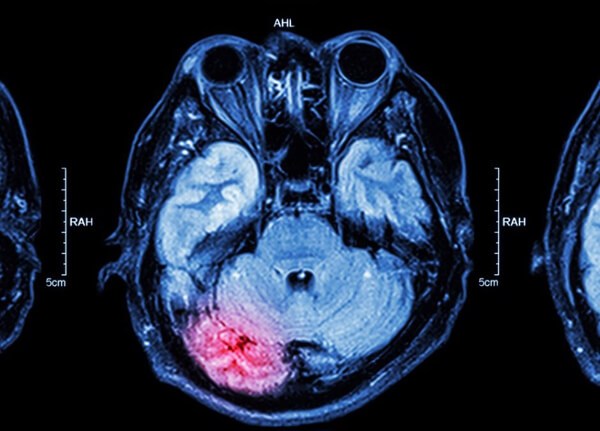

뇌출혈

뇌출혈은 말 그대로 뇌혈관의 출혈이 원인이 되어 일어나는 것으로, 뇌혈관장애, 뇌일혈이라고도 한다. 뇌졸중을 일으키는 대표적 질환인 뇌출혈의 공통된 초기 증상은 두통과 구토다. 두통이 반복적으로 일어나면서 극심한 고통을 수반하는 경우에는 병원에 가보는 게 좋다.